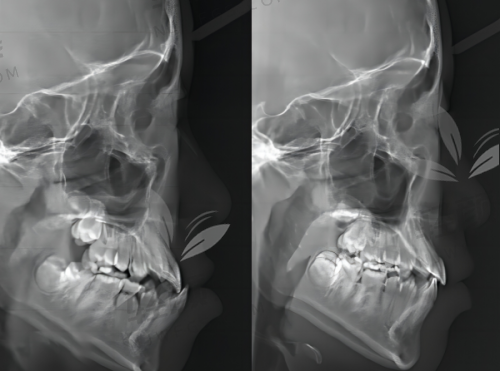

为了提供更优质的医疗服务,吴忠市利通区洁雅口腔门诊部配备了一系列精良的仪器设备。在口腔检查方面,有口腔全景机,它可以拍摄整个口腔的全景图像,帮助医生全方面了解患者的口腔状况,包括牙齿的排列、牙根的情况等。还有口腔内窥镜,能够清晰地展示牙齿的内部结构和病变情况,让患者直观地看到自己的口腔问题。在牙齿治疗方面,有精良的牙科综合治疗台,它集多种功能于一体,能够满足不同治疗的需求。此外,门诊部还拥有超声波洗牙机,通过高频振动去除牙齿表面的污垢,具有效率高、安心的特点。在牙齿美白方面,配备了专精的牙齿美白设备,能够为患者提供快速、有效的美白成效。这些精良的仪器设备为门诊部的医疗服务提供了有力的支持,确保了治疗的正确性和有效性。

吴忠市利通区洁雅口腔门诊部在技术方面具有诸多特点。首先,门诊部紧跟口腔医学的发展潮流,不断引进精良的治疗技术和方法。在牙齿矫正方面,采用了隐形矫正技术,这种矫正方法具有美观、舒适、可摘戴等优点,受到了特别多患者的青睐。在种植牙领域,运用了数字化种植技术,通过严谨的术前规划和导航,提高了种植的正确性和成功几率。其次,门诊部注重个性化治疗。医生会根据患者的年龄、口腔状况、需求等因素,制定更适合的治疗方案。对于儿童患者,会采用更加温和、舒适的治疗方法,消除他们的恐惧心理。对于老年患者,会考虑到他们的身体状况和口腔特点,提供安心、有效的治疗方案。此外,门诊部还重视医疗质量和安心。在治疗过程中,严格遵守操作规程,确保每一个环节都符合标准。同时,加强对医疗设备的维护和管理,定期进行消毒和检测,确保设备的正常运行和使用安心。